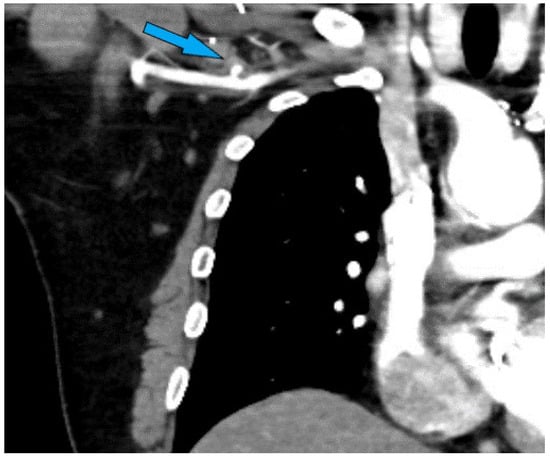

A patient in his 40s initially presented with chest pain, initially treated for pericarditis. A cardiac MRI revealed a Type A aortic dissection, leading to their first surgery for repair, including resuspension of the aortic valve and ascending aortic interposition graft with arch septectomy. Following this, they experienced complications, including a pseudoaneurysm at the proximal anastomosis of the ascending aorta, necessitating multiple redo surgeries. These included aortic valve replacement, ascending aorta replacement with a Gelweave (Terumo Aortic, Sunrise, FL, USA) graft, and installation of a Thoraflex Hybrid (Terumo Aortic, Sunrise, FL, USA) graft under deep hypothermic circulatory arrest three years later. Further complications led to additional interventions, including refashioning of an axillary extra-anatomical bypass and management of an infected sternal collection. Persistent issues, such as an infected pseudoaneurysm compressing the right axillary graft and a recurrent proximal aortic one, resulted in their referral for complex redo surgical intervention. The extensive medical history also included hypertension, hypercholesterolemia, atrial fibrillation, and recurrent postsurgery infections, complicating his treatment pathway (Figure 7).

Figure 7.

Preoperative CTA illustrating the presence of an extra-anatomical bypasses, chronic mediastinal infection, and pseudoaneurysm.